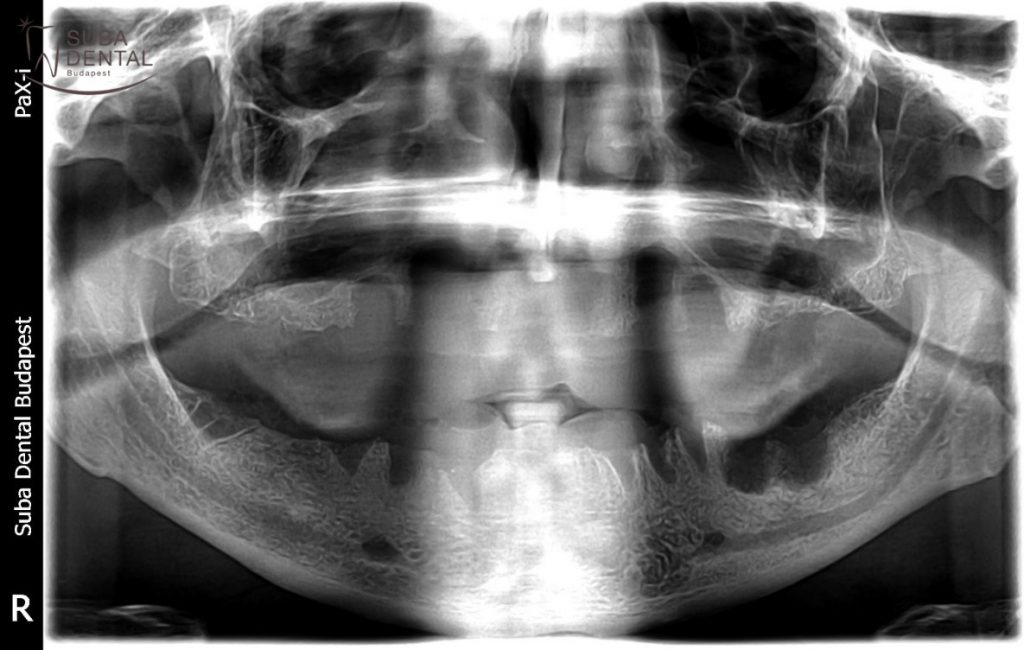

Panoramic radiography was performed and intraoral X-ray scans were recorded of the current condition in order to determine the cause of the problem. It was readily visible in the X-rays recorded that both the patient’s teeth and the implants previously received were beyond repair and the inflammation, infection, bone resorption and peri-implantitis around them indicated the removal thereof (explant surgery). These dental foci may, among other things, cause heart disease, hair loss, dermatological issues and joint complaints.

Due to the omission of regular check-ups and heavy smoking all the implants had to be removed as they had all developed peri-implantitis around them. Bridge replacement was out of the question. The dark shadow around the implants signifies peri-implantitis.